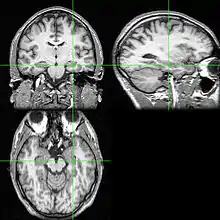

Recent research using neuro-imaging technology including PET and fMRI scanning has shown that there is an extensive amount of distributed brain activation during the process of episodic encoding and retrieval. Among the various regions, the two most active areas during the constructive processes are the medial temporal lobe (including the hippocampus) and the prefrontal cortex.[15] The Medial Temporal lobe is especially vital for encoding novel events in episodic networks, with the Hippocampus acting as one of the central locations that acts to both combine and later separate the various features of an event.[16][17] Most popular research holds that the Hippocampus becomes less important in long term memory functioning after more extensive consolidation of the distinct features present at the time of episode encoding has occurred. In this way long term episodic functioning moves away from the CA3 region of the Hippocampal formation into the neocortex, effectively freeing up the CA3 area for more initial processing.[17] Studies have also consistently linked the activity of the Prefrontal Cortex, especially that which occurs in the right hemisphere, to the process of retrieval.[18] The Prefrontal cortex appears to be utilized for executive functioning primarily for directing the focus of attention during retrieval processing, as well as for setting the appropriate criterion required to find the desired target memory.[15]